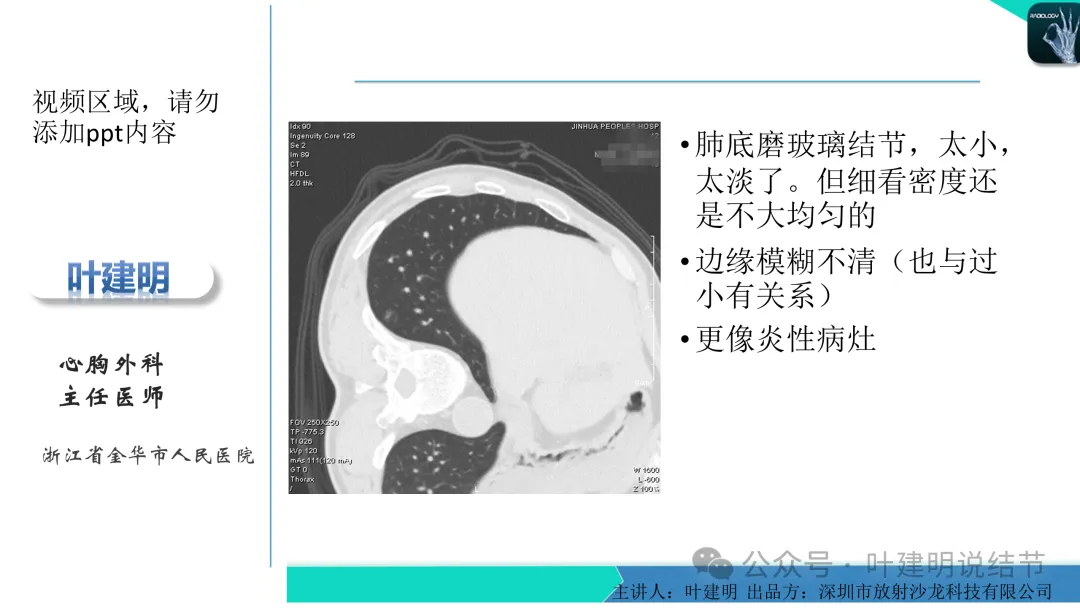

当地说考虑微浸润性腺癌的左下主病灶影像连续层面展示:

病灶出现,显模糊。

上图层面轮廓较清,但密度很淡,似见血管走行,但靠左前方的似条状磨玻璃密度与血管连着的到底是血管分支还是结节的一部分,其实并不确切。如果其实是血管分支,那病灶与它之间就不是空泡。

病灶在此层整体边缘显糊,灶内有空泡似的,瘤肺边界欠清。

边缘不平,还是灶内多发小空泡?邻近血管与之紧贴,但血管无异常走行。病灶密度很低,显糊。

中间所谓空泡更像是细支气管扩张,内壁非常光滑且圆形。

病灶边缘区淡而模糊。

这个病灶会是微浸润性腺癌吗?当然没有病理诊断,我也不能说百分之百必不会,但这样的病灶已经风险大到必得尽快手术切除干预了吗?显然还早着呢:1、影像不是典型的结节状;2、边缘与轮廓模糊不清;3、灶内似有细支气管扩张(更容易是细支气管扩张伴少许周围炎或肺泡上皮增生);4、血管邻近走但无牵拉影响;5、没有实性成分,没有锐利毛刺,没有胸膜牵拉,没有血管进入,没有任何倾向风险性高的影像特点。我一直强调:肺结节是否要干预处理,不要纠结于最后病理是什么,而要看风险高低;而风险高低的最重要术前判断依据一是随访有无进展,二是有没有实性成分。只要没有肉眼可见的影像上的实性成分,风险就是低的!何况病理也是人看的,原位还是微浸润,不典型增生还是原位有时也在一念之间。